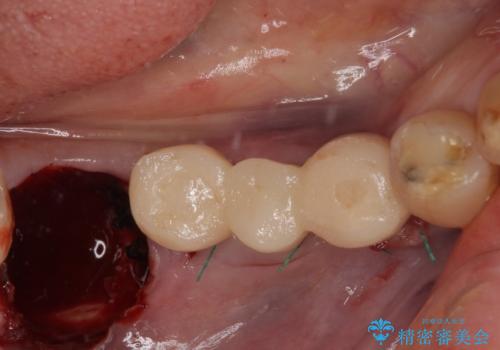

インプラント埋入時に仮歯を装着させることが可能な安定値が得られたため、その日に仮歯の装着を行いました。

咬合時に仮歯が噛み合わないように調整はしたのですが、反対側の奥歯も欠損していることから、食事中積極的に仮歯で咀嚼をしてしまい、2週間後には大きく安定値が低下してしまいました。